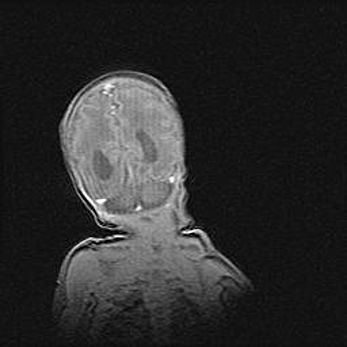

Ниже представлена  галерея МРТ снимков, полученных с применением LMT неонатальных матричных РЧ катушек. Также каждая группа МРТ снимков сопровождается информацией о пациенте (диагноз, возраст, вес, пол, срок гестации) и краткой сопроводительной расшифровкой диагноза.

Церебральная ишемия II.

Возраст: 5 дней

Вес: 3400 г

Пол: женский

Окружность головы: 35 см

Срок гестации: 39 недель

Церебральная ишемия – это заболевание, характеризующееся недостаточностью (гипоксией) либо полным прекращением (аноксией) снабжения мозга кислородом по причине закупорки одного или нескольких сосудов. Это приводит к  что метаболическим расстройствам различной степени тяжести в тканях головного мозга, развитию коагуляционных некрозов и гибели нейронов.